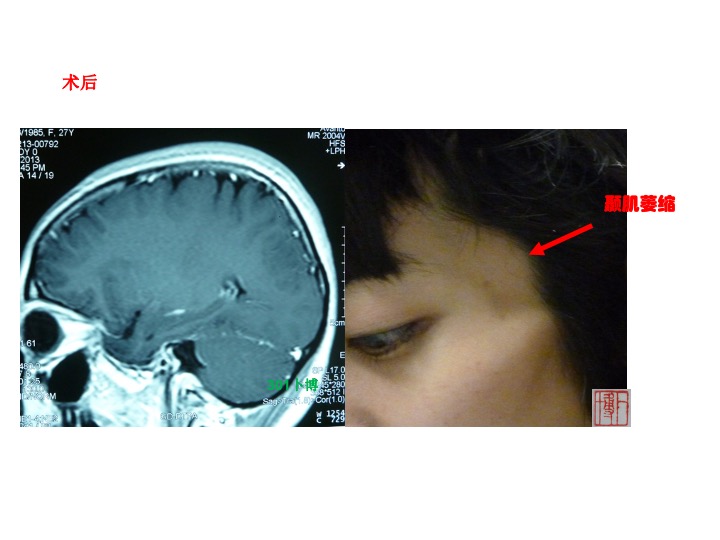

病例2,女性,26岁。主因头痛左侧面部麻木半年个月入院。查体:左侧面部痛温觉减退,左侧咀嚼肌肌轻度萎缩。MRI示左侧中颅窝底鞍旁颞下窝长T1长T2占位,可明显强化。大部分肿瘤位于颞下窝。术后强化MRI提示肿瘤切除理想,同时可见患者颞肌萎缩。